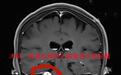

完善检查后,陈婆婆被确诊为右侧桥小脑角区听神经瘤。该院神经外科一病区医生陈阳表示,这类脑肿瘤主要发源于前庭神经,会引起面神经、前庭听神经的损伤,主要以耳鸣、耳聋为首发症状。老人回忆起,一年前她出现右耳听力下降,因为没有影响正常生活,她也没太在意,哪知近期出现了感觉异常,以及类似小虫子在爬的“蚁走感”。陈阳表示,为避免肿瘤占位效应加重,造成舌咽、小脑功能障碍,甚至脑积水等病变,要尽快手术切除脑瘤。

在患者及家属的认可下,病区主任岑波教授高度重视,立即组织当期驻院专家、天坛神经外科教授关树森及病区医师周军格、熊寂丞、陈阳共同为陈婆婆进行手术,并全切了直径达3厘米的瘤体,同时确保了面神经、后组颅神经等神经组织完好。术后,老人面部功能保留良好,右侧听力及面部感觉等显著恢复,“蚁走感”消失,即将拆线出院。